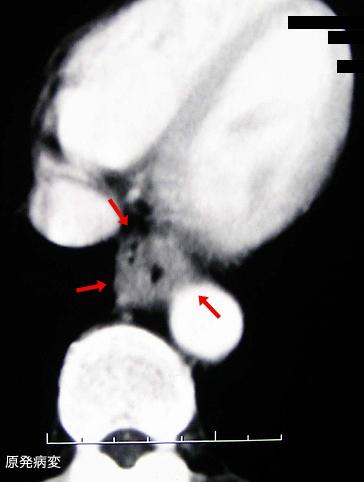

Criteria of Hist.ClassificationMalignant epithelial tumor/Squamous cell carcinoma

LocationEsophagus/Lower third

Technique, MethodCT

Macroscopic TypesType 3 Ulcerated type with infiltration/

Size35 - 40

Depth of Tumor Invasionserosa (adventitia)